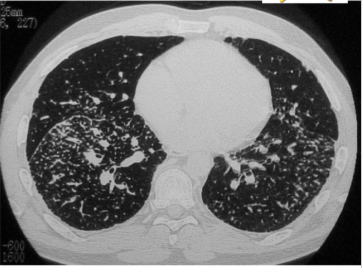

Is this UIP?

No, this is not UIP because this is upper-lobe predominant fibrosis